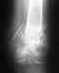

Проконсультируйте, пожалуйста, о методах лечения, нет ли необходимости операции при компрессионном стабильном неосложненном переломе L2 позвонка. Так же имеется Диффузное выбухание м/п диска L4-L5(из заключения МРТ).

Описание МРТ: Выявляются дистрофические изменения 1-й стадии в исследуемых сегментах в виде дегидрации ядер м/п дисков без уменьшения их высоты. Клиновидная деформация 1-й степени, отек тела L2 позвонка. Дуга позвонка не изменена. В сегменте L4-L5 диффузное выбухание м/п диска, переднезадним размером 3мм, с легкой деформацией передней поверхности дурального мешка и сужением м/п отверстий 1-й степени.Переднезадний размер позвоночного канала на уровне тела L4 позвонка 17мм. Каудальные сегменты спинного мозга и корешки "конского хвоста" не изменены. Паравертебральных изменений не выявляется. Заранее,СПАСИБО.